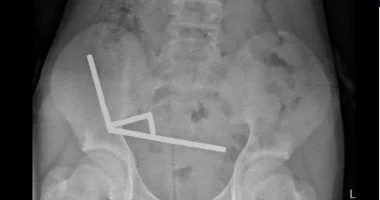

أظهرت الأشعة السينية أن المغناطيسات رتبت نفسها في أربع خطوط مستقيمة داخل الأمعاء، وتوزعت في أجزاء مختلفة من الأمعاء وكانت ملتصقة ببعضها بفعل القوى المغناطيسية.